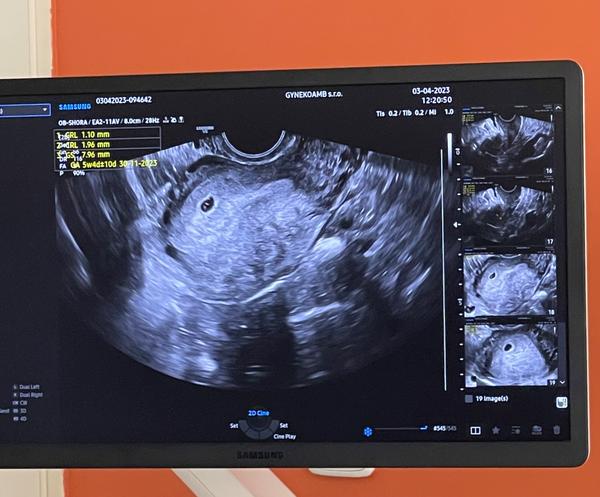

chtěla bych se zeptat, jestli na ultrazvuku je vše v pořádku - hodnota hCG v pondělí byla 3500.

Dle utz jsem nyní 5+6tt.

ano, co lze vidět z obrázku a z toho, co píšete, na ultrazvuku bylo vidět nejspíše nitroděložní těhotenství a drobný embryonální pól. Hodnota hCG tomu odpovídá. Nepíšete, zda již byla vidět srdeční akce, ale pokud ne, tak při takto časné graviditě to ultrazvuk ještě vidět nemusí. Je na místě kontrola s odstupem, jak máte plánováno k potvrzení růstu těhotenství a přítomnosti srdeční akce.

Ještě doplním, teď jsem si všiml, že jste se ptala už před pár dny ke stejnému snímku ohledně toho, zda v děloze nejsou dva zárodky (2x CRL). K tomu se ze statického malého snímku nelze vůbec vyjádřit, vyšetření v reálném čase snímek nenahradí.